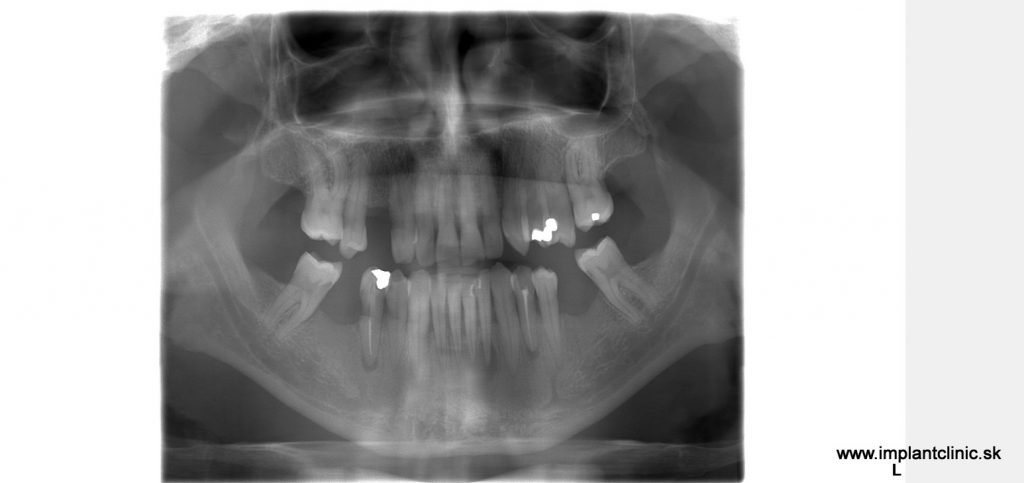

Tento pán prišiel s narušenou žuvacou funkciou. Po konzultácii s implantológom sme navrhli plán: zaviedli sme 6 zubných implantátov a nasadili 14-členný mostík do oboch čeľustí. Ošetrenie sme rozdelili na dve sedenia, aby sme zabezpečili pohodlie a plynulý priebeh.